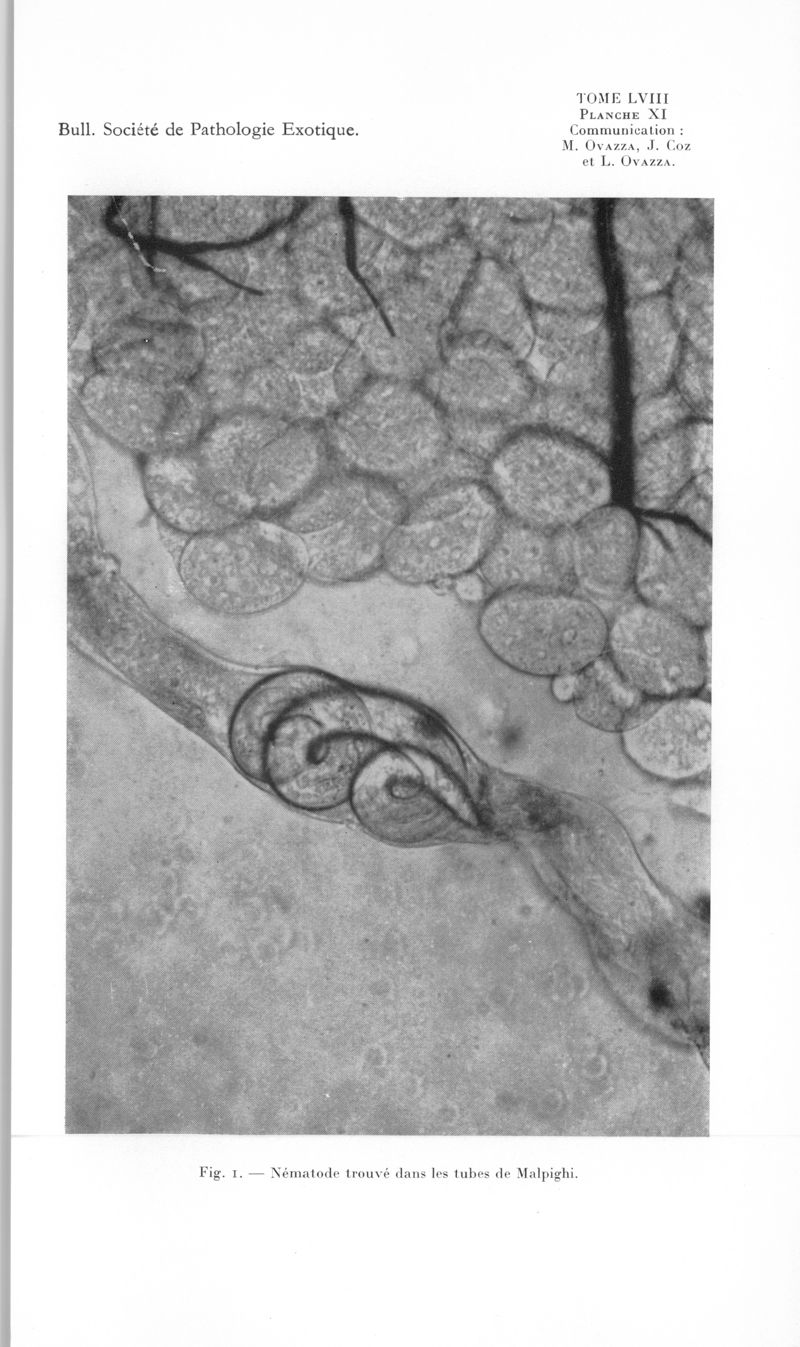

Bulletin de la Société de pathologie exotique et de ses filiales

1965, tome 58. - Paris : Masson, 1965.